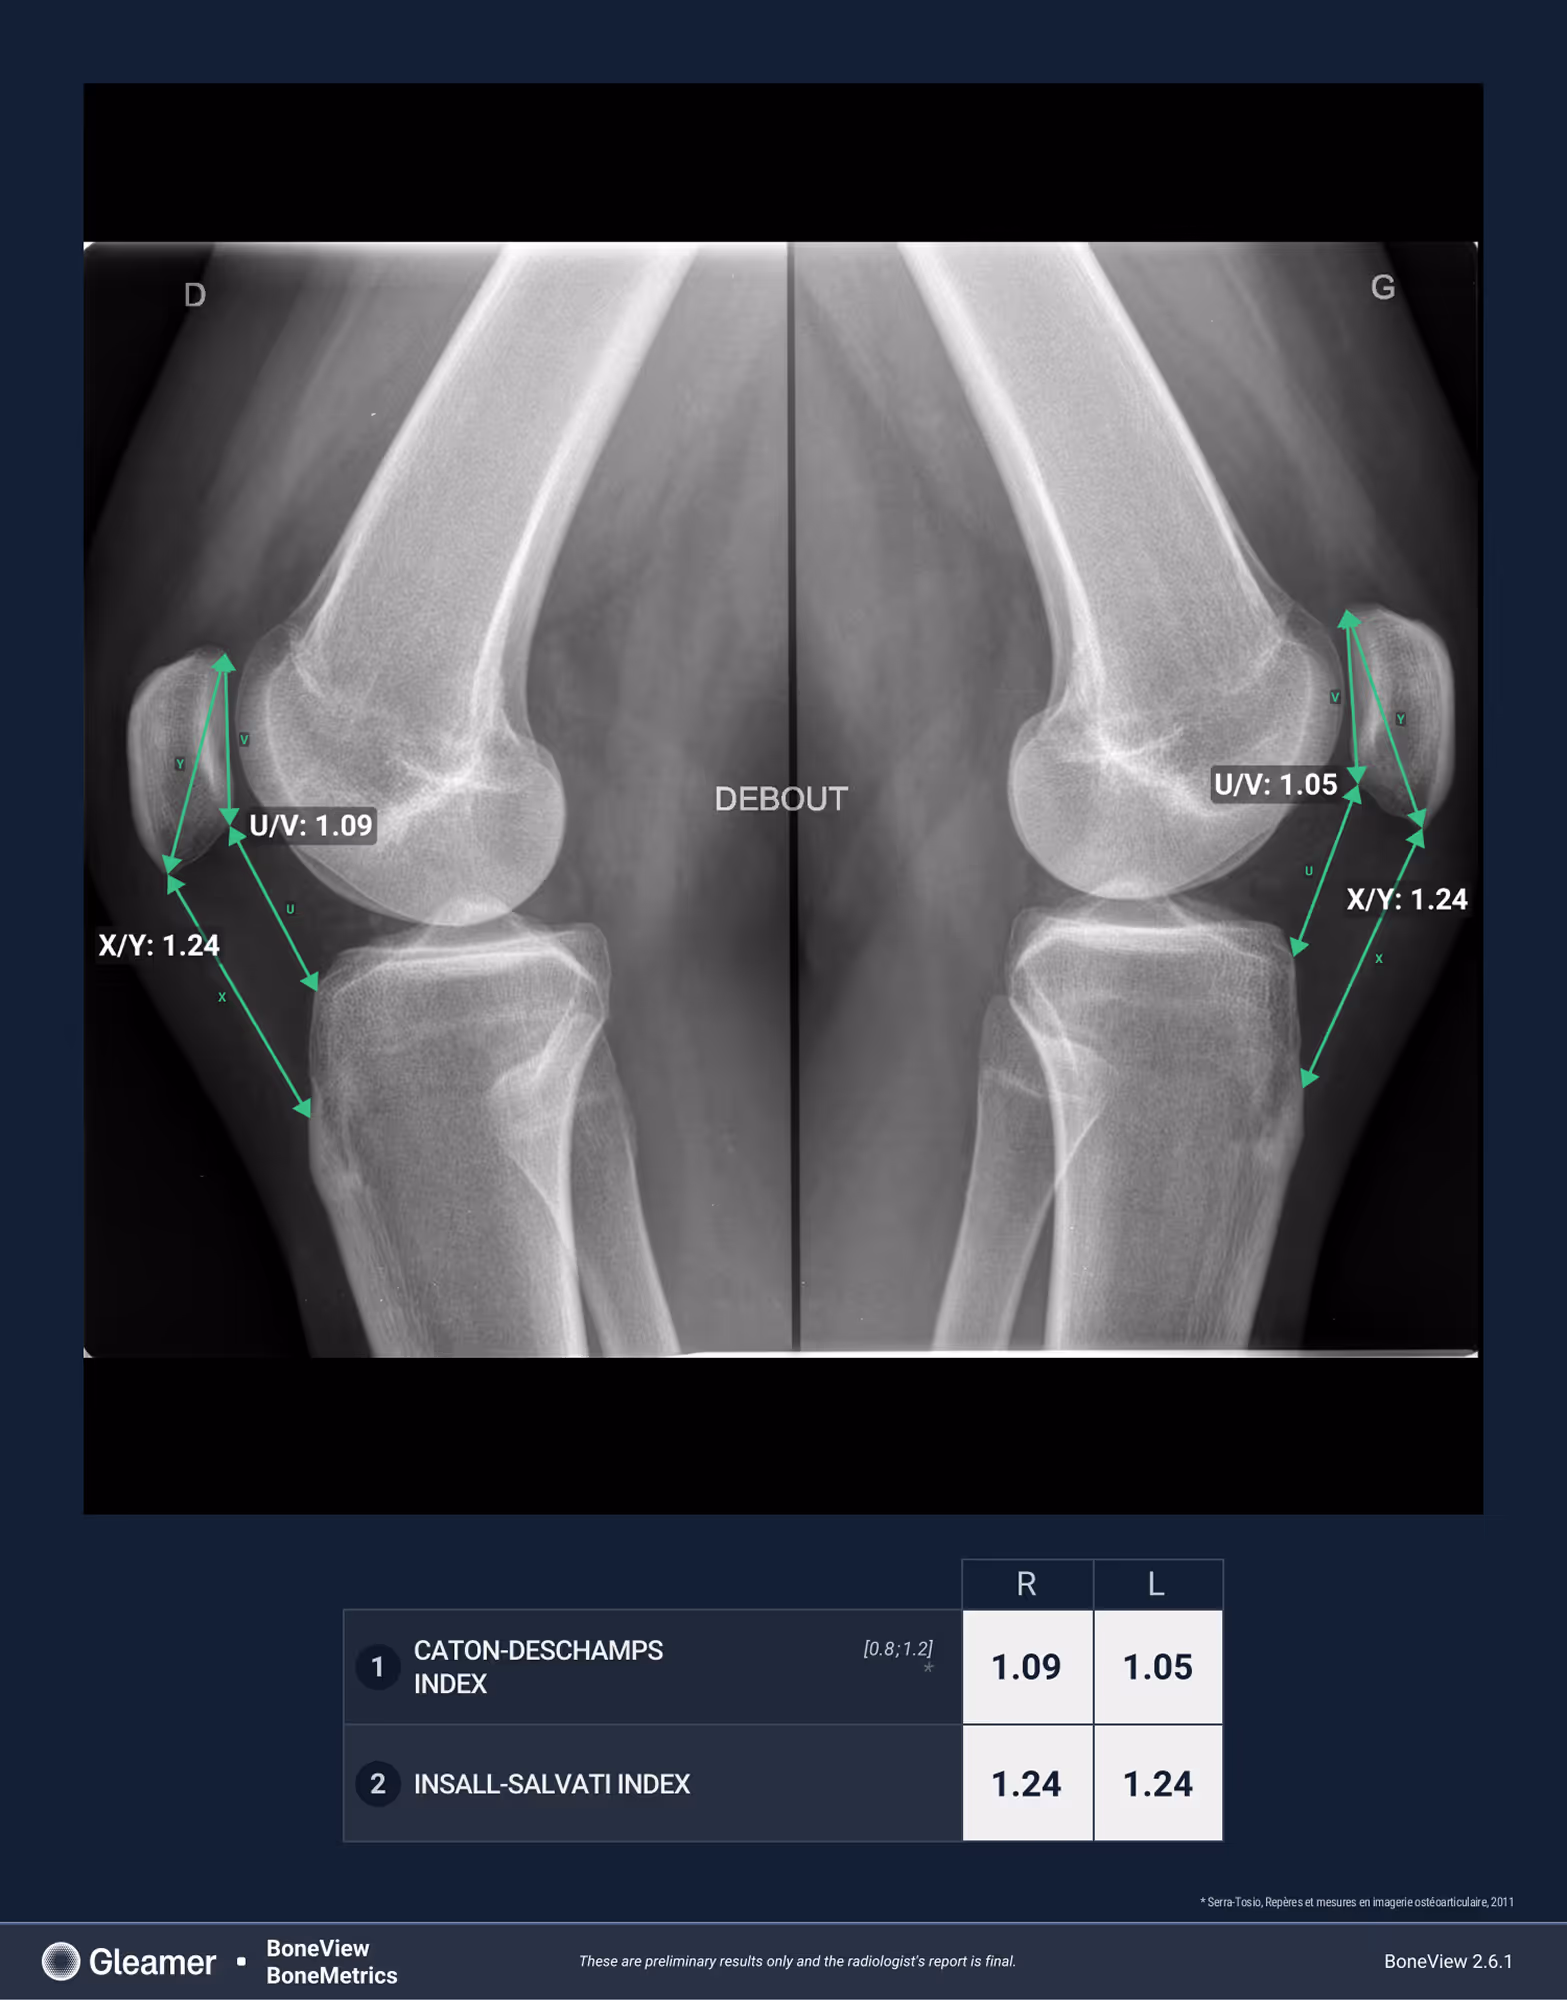

Indication

A 15-year-old male presenting with non-specific knee pain.

Results

BoneMetrics measured the Caton-Deschamps and Insall-Salvati indices, showing values within the normal range.

Caton-Deschamps index

Insall Salvati index